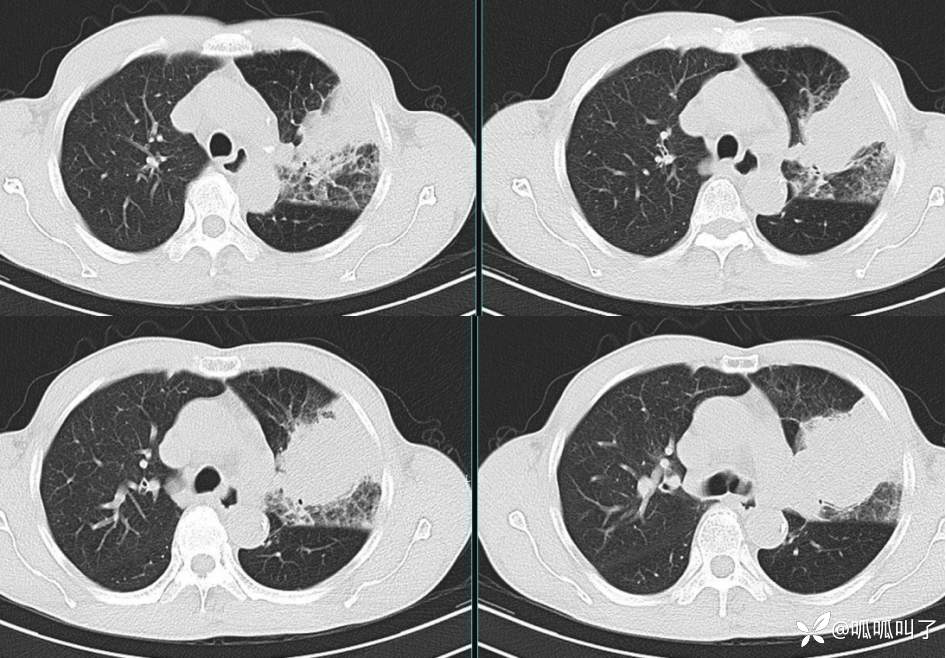

胸部CT平扫和增强: